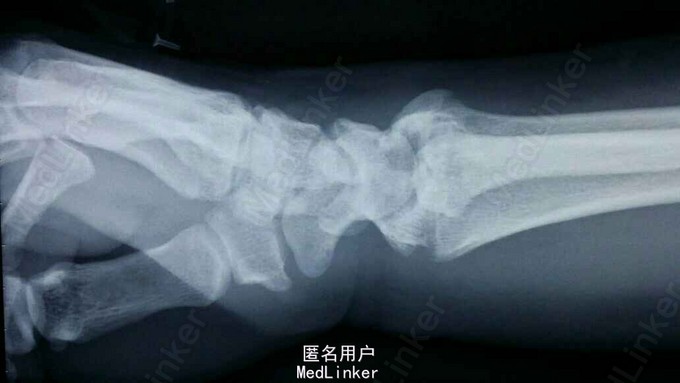

患者于2015年8月18日从高处坠落(约7米)伤及双碗,肿胀,畸形,活动受限。

双碗畸形明显,肿胀明显,可见明显皮下淤血,压痛阳性,可触及明显骨察感及骨察感,左手有明显正中神经压迫症状。

诊断:双尺桡骨远端粉碎性骨折 治疗:入院后,给予手法复位夹板固定,左手神经症状明显缓解,给予对症治疗,消肿后,于2015年8月27日行手术治疗。